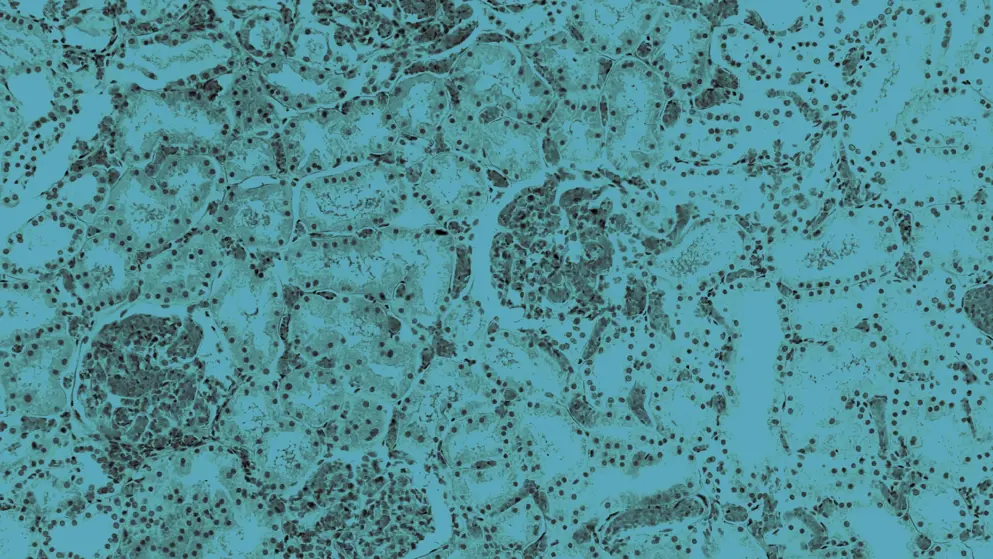

Polycystic kidney disease

Polycystic kidney disease (PKD) is a genetic disorder inherited as an autosomal dominant or recessive trait1. Autosomal dominant PKD is one of the most common genetic disorders and the fourth leading cause of end-stage kidney disease (ESKD) in children and adults2,3. The prevalence of autosomal dominant PKD has been reported to be between 1 in 400 and 1 in 1000 and it is predicted to affect more than 10 million people worldwide3. Autosomal recessive PKD is less common but more severe, and has an estimated prevalence of 1 in 20,0004.

Autosomal dominant PKD is caused by mutations in the PKD1 or PKD2 genes, which encode the proteins polycystin (PC) 1 and PC2, respectively. It is generally thought to manifest in adulthood, but there is increasing awareness that the clinical course can also begin in childhood5. There is wide variation in the phenotype of ADPKD, ranging from asymptomatic to severely ill5. Autosomal recessive PKD is caused primarily by mutations in the polycystic kidney and hepatic disease 1 (PKHD1) gene. It is typically identified in the late stages of pregnancy or at birth; 30–50% of affected neonates die soon after birth4. Both forms of PKD cause renal and extrarenal manifestations3,5. In the kidneys, parenchymal destruction leads to ESKD, requiring dialysis or kidney transplantation in more than half of patients by the age of 60 years6.